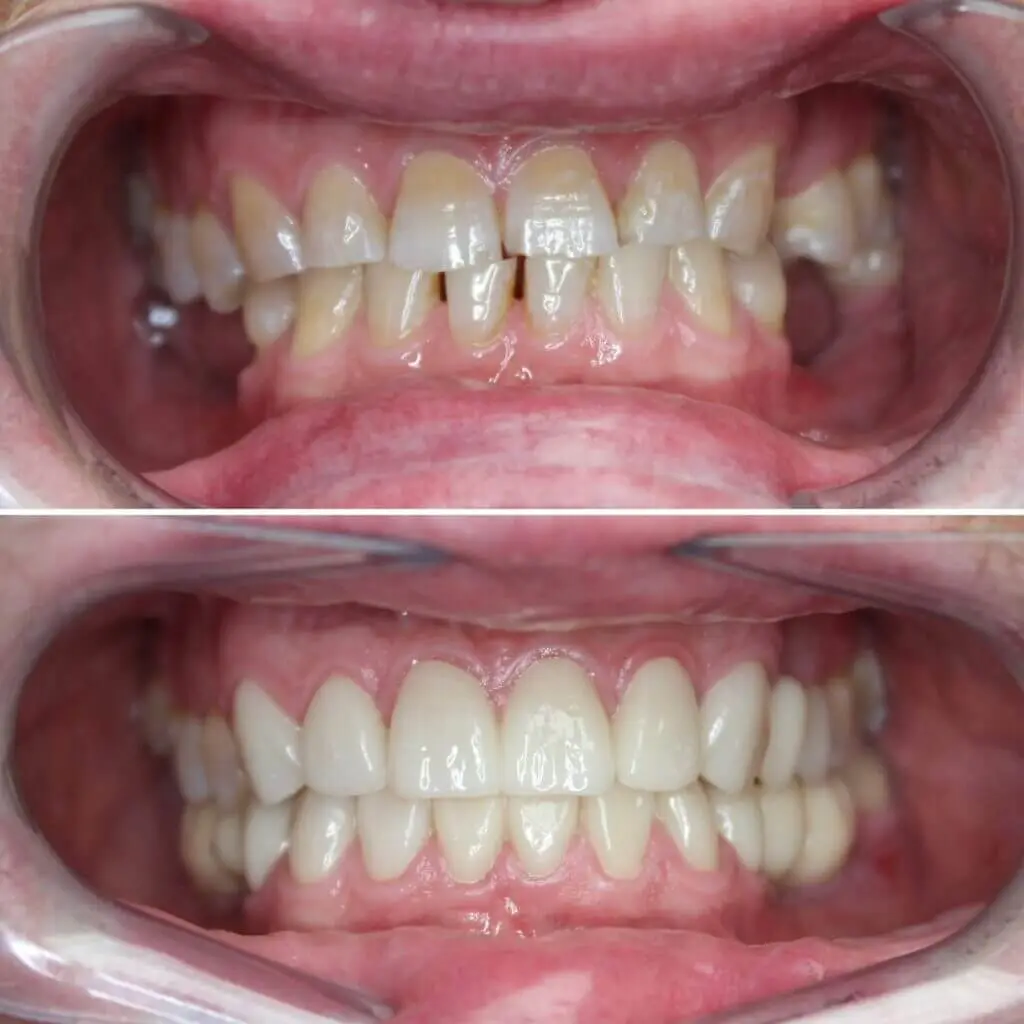

Cirkon koronák

Két felső nagymetsző töredezett, elszíneződött gyökérkezelt fogak

voltak, rossz állapotúak voltak. Helyreállításuk üvegszálas csapozást

követően szóló anatómikus cirkon koronákkal történt. Összesen 4

korona.